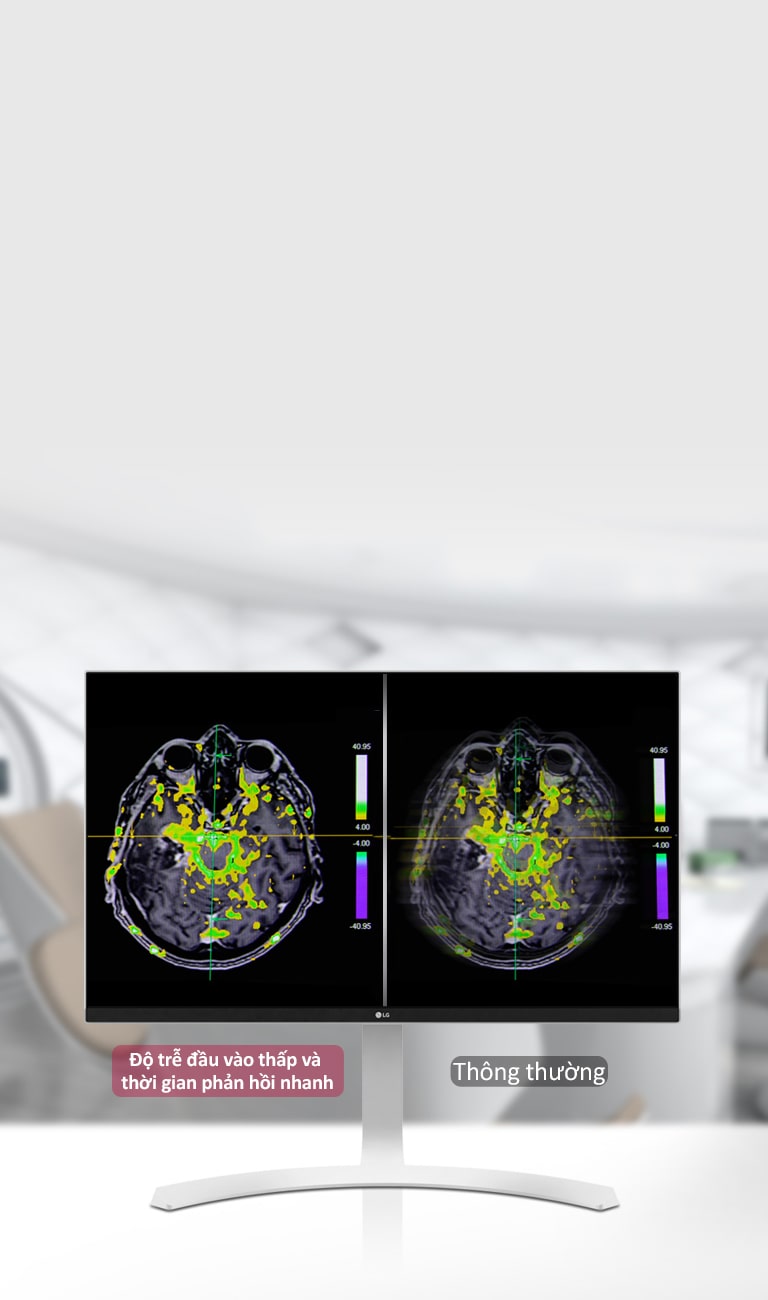

Thời gian phản hồi

5ms (GtG ở chế độ Nhanh hơn)